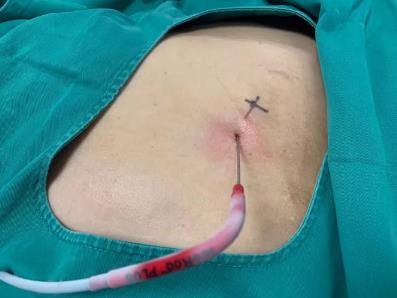

2017年9月29日,從CT影像看到右腎情況更為嚴重。為減緩腫瘤增長的速度,專家進行商議后,最終決定由牛立志教授主刀為安圖叔叔進行了右腎腫瘤冷凍消融術。手術開始后,牛立志教授在CT和超聲引導下,同時使用兩根冷凍針固定病灶,精準滅活腫瘤;術后很成功無不良反應。術后一周進行第二次雙腎腫瘤冷凍消融術。安圖叔叔兒子笑道:“當時真的很緊張,醫生勸慰我無須擔心,都交給他們,我們都很清楚知道父親的病情,真的很感謝也很慶幸我父親遇到復大的醫護人員,免受開刀之痛。住院期間醫護人員很盡心盡力的照顧父親,手術的成功離不開他們的辛勞付出。”

冷凍治療手術中